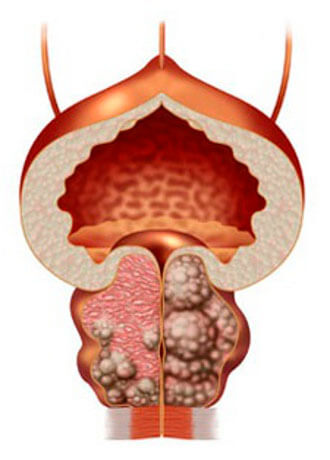

Prostatitis normal

Adenoma prostática

Si no curar la prostatitis, se desarrolla muy rápido y siempre lleva a la adenoma de la próstata ("la muerte masculina")